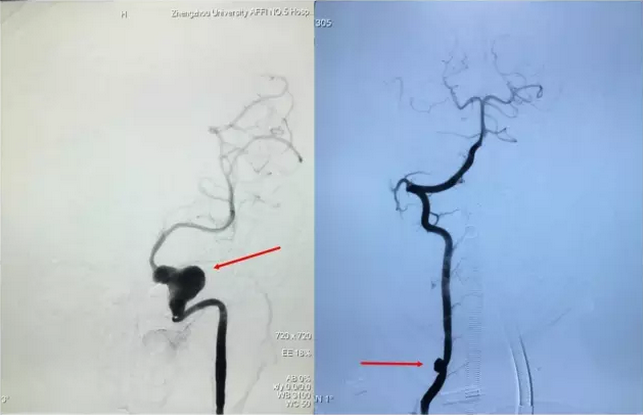

当家人见到寿记新教授并说明来意后,寿记新教授仔细询问了孩子的情况,并分析了孩子的检查结果。凭借多年的临床经验寿记新教授立即判断孩子得的不单纯是动脉瘤,而是肌纤维发育不良(FMD)。于是立刻收入院,安排梁博医师和周少龙医师为孩子做了全脑血管造影检查,结果和寿记新教授判断的一模一样——肌纤维发育不良(FMD),颅内多发动脉瘤:左侧颈内动脉虹吸段巨大瘤样扩张,左侧颈外动脉多发囊性动脉瘤,左侧椎动脉V3段起始部、右侧椎动脉V2段数枚动脉瘤。(图1)

图1术前脑血管造影:颅内外多发动脉瘤。